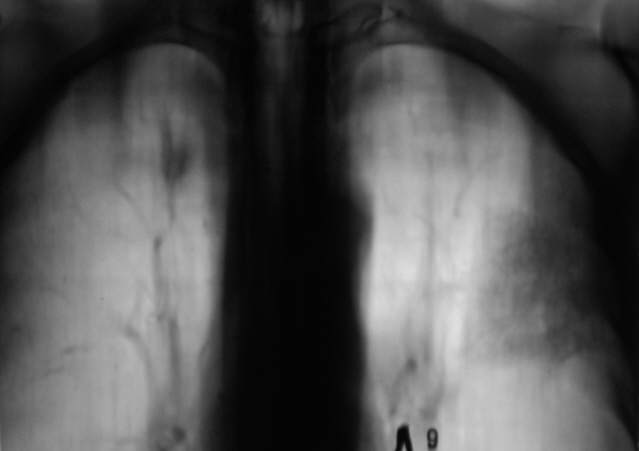

Произведена томография.

на боковых снимках слева ощущение уменьшенного S2 имеет четкую конусовидную форму вершиной обращенный к корню, пневматизация его нарушена. В области головки левого корня дополнительная тень?Справа в верхней доле округлая тень с четкими, неровними контурами с сосудистой "дорожкой" к корню.